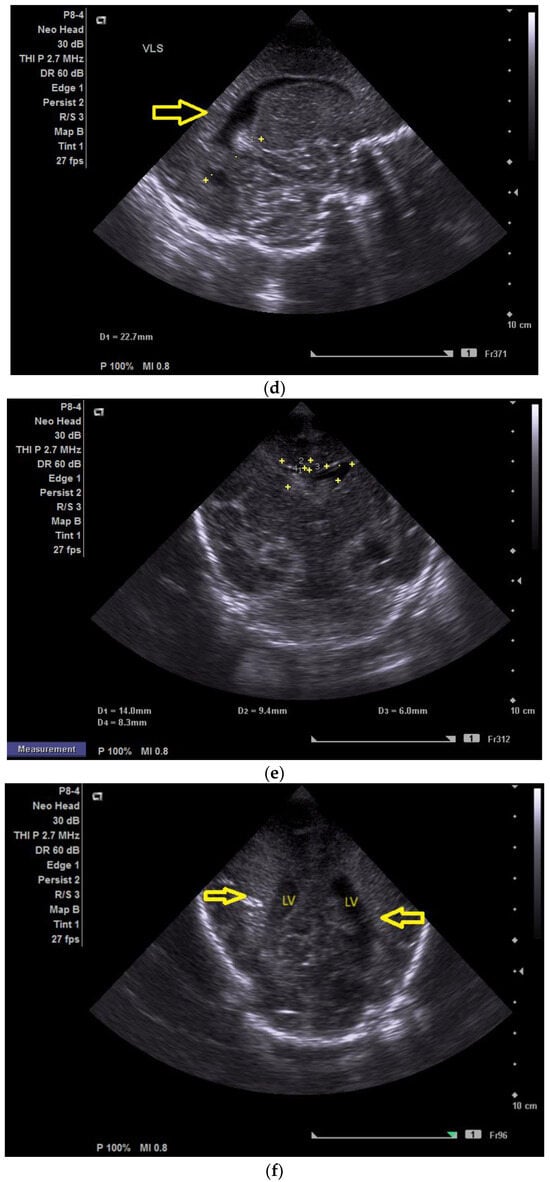

The day one of life CUS revealed the presence of a left frontal conatal cyst with no other modification (Figure 2a).

(a) Day one. Cranial ultrasound. Sagittal view. A left frontal conatal cyst can be observed. IHF—interhemispheric fissure. CG—cingulate gyrus. CC—corpus callosum. CSP—cavum septum pellucidum. TCG—thalamic-caudate groove. MF—Monroe foramina. SF—Sylvian fissure. Yellow arrow—conatal cyst (personal image collection). (b) Day three. Cranial ultrasound. Coronal view. Bilateral ventricular dilatation. Yellow arrows—hyperechoic images can be seen at the level of the thalamic-caudate groove and within the ventricles (personal image collection). (c) Day three. Cranial ultrasound. Coronal view. Orange arrows—bilateral periventricular hyperechoic images (personal image collection). (d) Day three. Cranial ultrasound—Doppler examination. Sagittal view. CC—corpus callosum. FL—frontal lobe. LV AH—lateral ventricle anterior horn. V 3—third ventricle. V 4—fourth ventricle. OL—occipital Lobe. Yellow arrow—presence of color Doppler signal within the Sylvian aqueduct (personal image collection). (e) Day 19. Cranial ultrasound. Sagittal view (left). Yellow arrows—conatal cysts. Pink arrows—PVL lesions (personal image collection). (f) Day 19. Cranial ultrasound. Sagittal view (left). Yellow arrows—conatal cysts. Pink arrows—PVL lesions (personal image collection). (g) Follow-up examination at term corrected age. Cranial ultrasound. Coronal view. Slight dilation of the lateral ventricles. IHF—interhemispheric fissure. CG—cingulate gyrus. CC—corpus callosum. CSP—cavum septum pellucidum. LV—lateral ventricle. MF—Monroe foramina (personal image collection). (h) Second follow-up examination. Cranial ultrasound. Coronal view. Dilation of interhemispheric fissure and subarachnoid space. D1—sinus–cortical width measurement. D2—interhemispheric width measurement. D3—cranio-cortical width measurement (personal image collection). (i) Third follow-up examination. Cranial ultrasound. Coronal view (left). D1—dilation of interhemispheric fissure. D2, D3—Levine index measurement (personal image collection). (j) Cranial ultrasound. Sagittal view (right). Normal brain structures (personal image collection). (k) Head circumference-for-age. “X” symbols represent the measurements performed from birth and follow-up examinations (personal image collection) [28].

On day three of life, the CUS displayed a bilateral germinal matrix hemorrhage with more than 50% of the ventricular volume being occupied by blood. Periventricular hyperechoic images could be observed as well (Figure 2b,c).

On the fourth day of life, a Doppler examination showed the presence of a signal within the third ventricle (Figure 2d).

A series of four lumbar punctures were performed during the patient’s in-stay to relieve the intracranial pressure—expressed as a bulging fontanelle. The first three lumbar punctures presented hemorrhagic CSF, while the last lumbar puncture showed sero-citrine CSF. Afterwards, the ventricular dimensions stabilized; however, small visible PVL lesions were visible on the CUS examination, in addition to the two conatal cysts that were observed (Figure 2e,f).

The first follow-up CUS examination was performed at the term-equivalent age (corrected gestational age) and revealed a slight dilation of the lateral ventricles (Figure 2g). The neurologic examination showed normal development for the corrected gestational age and mild plagiocephaly.

The next follow-up examination was performed two months from birth at the term-equivalent age and the CUS examination showed dilation of the interhemispheric fissure and the subarachnoid space (Figure 2h). Plagiocephaly, torticollis, mild motor development delay, and hypertonia in the lower limbs were observed.

Four months after the first follow-up examination, the CUS revealed normal brain structures. The general movement examination showed absent fidgety movements, while the neurological examination showed a global developmental delay with hypertonia of the limbs predominantly at the level of the left side of the body (Figure 2i,j).